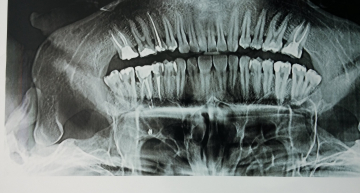

Мне 17 лет, стал часто болеть, то есть, заложеность носа выделение слизи из носа, делал КТ головного мозга заключение: двухсторонний гайморит, правостароний этмоэдит и сфеноорит, ещё написано "неравномерное покрытие слизистой в правой гайморовой пазухе", было лечение вроде прошло, но сейчас обратно, боли во лбу, переносице, врачи говарят "это хроническое у тебя будет так всегда" и лечение особо не проводили, выписывали капли в нос, таблетки.. И всё сейчас я заметил, что правая пазуха больше, чем левая, что это такое? Выпишите какие нибудь лекарства от этих болезней!!!!!! спасибо...